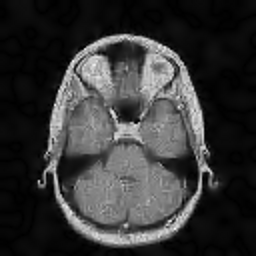

In this subsection, the MRI images from the built-in MRI dataset available in the MATLAB® toolbox have been used as test subjects. Specifically, the denosing algorithms have been tested using the axial slices number 4, 7 and 16 (shown in Figures 5, 5 and 5, respectively), which represent a spectrum of different cerebral structures. For quantitative comparison, simulated data have been obtained by subjecting the original test images to various levels of Rician noise.

Refer to caption

Figure 5: (a) Test slice #4, (b) Test slice #7 and (c) Test slice #16 of the MATLAB® MRI database.